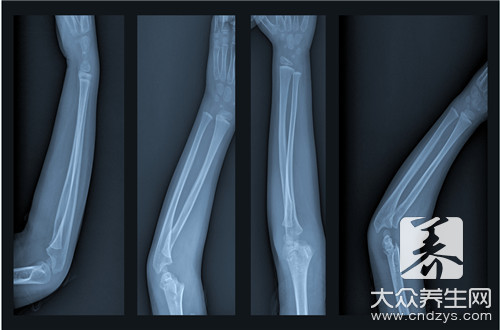

骨轉移疼痛的患者別到處問了,有辦法緩解。晚期骨轉移疼痛的患者,西醫一般用一些止痛藥,但效果都不太好,要搞清楚它為什么會疼痛。首先惡性腫瘤的產生,由于各種原因外感的內傷的多...